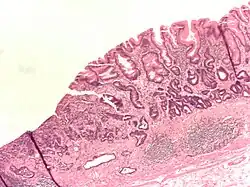

- Gastric adenocarcinoma is a malignant epithelial tumour, originating from glandular epithelium of the gastric mucosa. Stomach cancers are about 90% adenocarcinomas.[65] Histologically, there are two major types of gastric adenocarcinoma (Lauren classification): intestinal type or diffuse type. Adenocarcinomas tend to aggressively invade the gastric wall, infiltrating the muscularis mucosae, the submucosa, and then the muscularis propria. Intestinal-type adenocarcinoma tumour cells describe irregular tubular structures, harbouring pluristratification, multiple lumens, and reduced stroma ("back to back" aspect). Often, it is associated with intestinal metaplasia in neighbouring mucosa. Depending on glandular architecture, cellular pleomorphism, and mucosecretion, adenocarcinoma may present 3 degrees of differentiation: well, moderate, and poorly differentiated. Diffuse type adenocarcinoma (mucinous, colloid, linitis plastica or leather-bottle stomach) tumour cells are discohesive and secrete mucus, which is delivered in the interstitium, producing large pools of mucus/colloid (optically "empty" spaces). It is poorly differentiated. In signet ring cell carcinomas, the mucus remains inside the tumour cell and pushes the nucleus to the periphery, giving rise to signet-ring cells.

Poor to moderately differentiated adenocarcinoma of the stomach. H&E stain. -

Adenocarcinoma of the stomach and intestinal metaplasia. H&E stain.